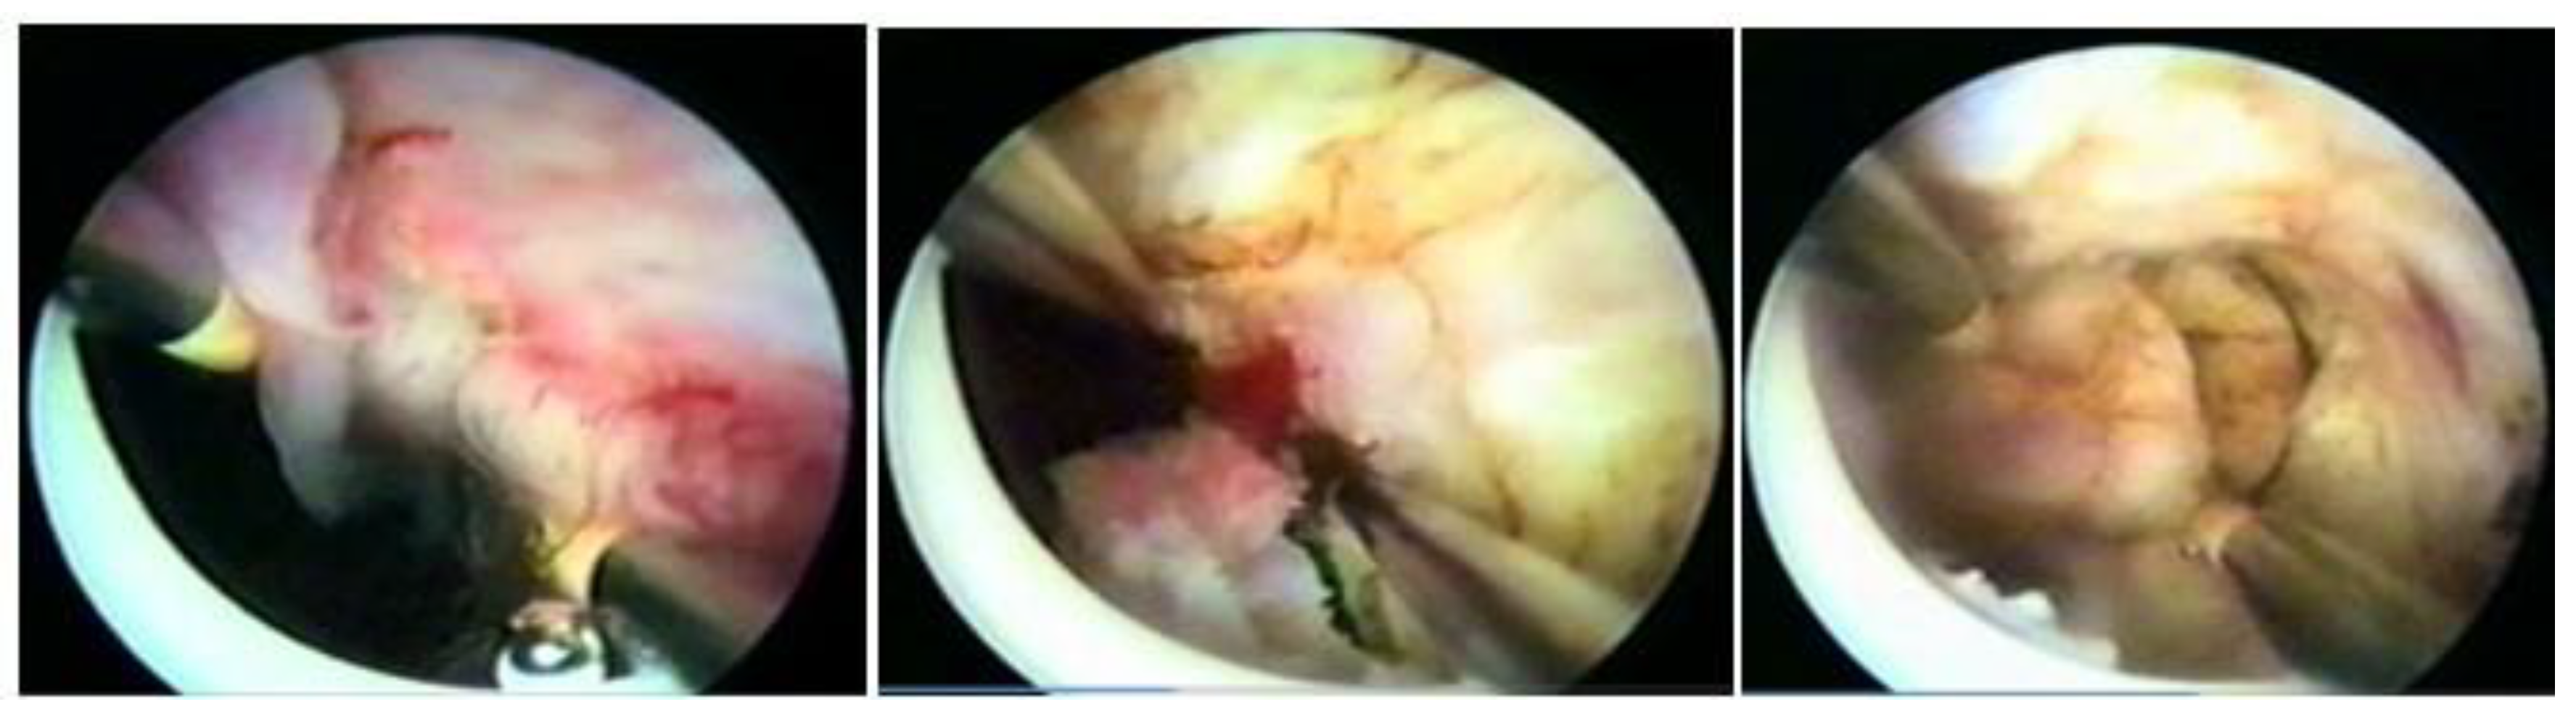

Ultrasonography (USG), especially transvaginal ultrasound (TVUS), is the routine exam and is usually the first one performed; it has good accuracy, easy access, and low cost, but it has a limited role in the presence of a large uterus or multiple nodules, as posterior acoustic shadowing makes it difficult to evaluate and count them. It is important in the evaluation of the intramural component of the myoma and the free myometrial mantle up to the serosa, but it is operator-dependent (Figure 2).

Hysterosonography, an ultrasound procedure performed with the uterus distended with saline solution for greater contrast and detailing of the uterine cavity, is more accurate than TVUS in identifying the uterine cavity and myometrial mantle (Figure 3).

Figure 2. Submucous myoma on ultrasound. * Submucosal fibroid.

Figure 3. Submucous myoma in sonohysterography.